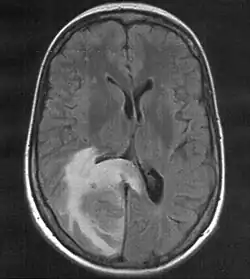

Hirnmetastase

MRT mit T2-Flair-Wichtung, die zugehörige PET-Untersuchung ist weiter unten abgebildet.

Kernstück der Diagnostik sind bildgebende Verfahren, wobei die Kernspintomographie (MRT) der Computertomographie (CT) überlegen ist.

Kernspintomographie

Die Kernspintomographie weist bei besserer Weichteildifferenzierung, insbesondere nach Gabe von Gadolinium als Kontrastmittel, eine deutlich höhere Sensitivität auf und ist somit geeigneter für die Suche nach Hirnmetastasen. So ist im Vergleich zur CT-Untersuchung die Rate der Patienten mit im MRT nachgewiesenen Hirnmetastasen mehr als doppelt so hoch.[8] Das gilt besonders für sehr kleine Befunde und Metastasen im Bereich der hinteren Schädelgrube. Die Kernspintomographie kann zur Abgrenzung gegen Hirnabszesse oder andere möglicherweise ähnlich imponierende Läsionen um eine Kernspinresonanzspektroskopie ergänzt werden.[9]